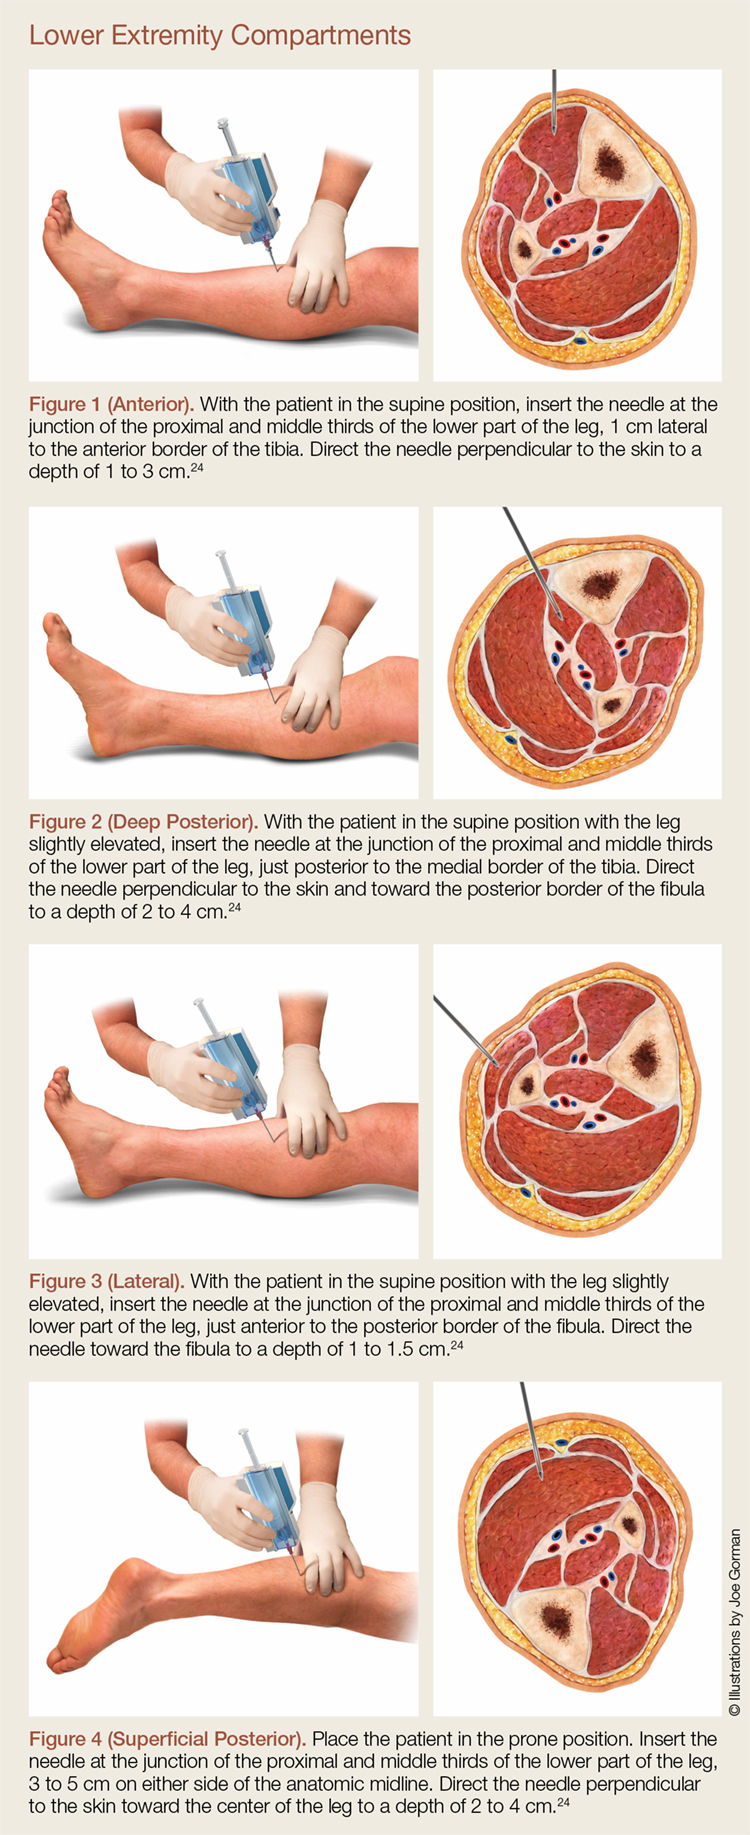

Is Delta Pressure Accurate For Compartment Syndrome County EM

Is Delta Pressure Accurate For Compartment Syndrome County EM

Chronic exertional compartment syndrome is a musculoskeletal condition brought on by exercise It can affect muscle compartments in any of your limbs but occurs most commonly in the lower legs The lower leg has four compartments and

Deep Posterior Compartment Syndrome Symptoms Causes Treatment

Compartment Syndrome Acute Chronic Anatomy And Operation

Compartment Syndrome Acute Chronic Anatomy And Operation